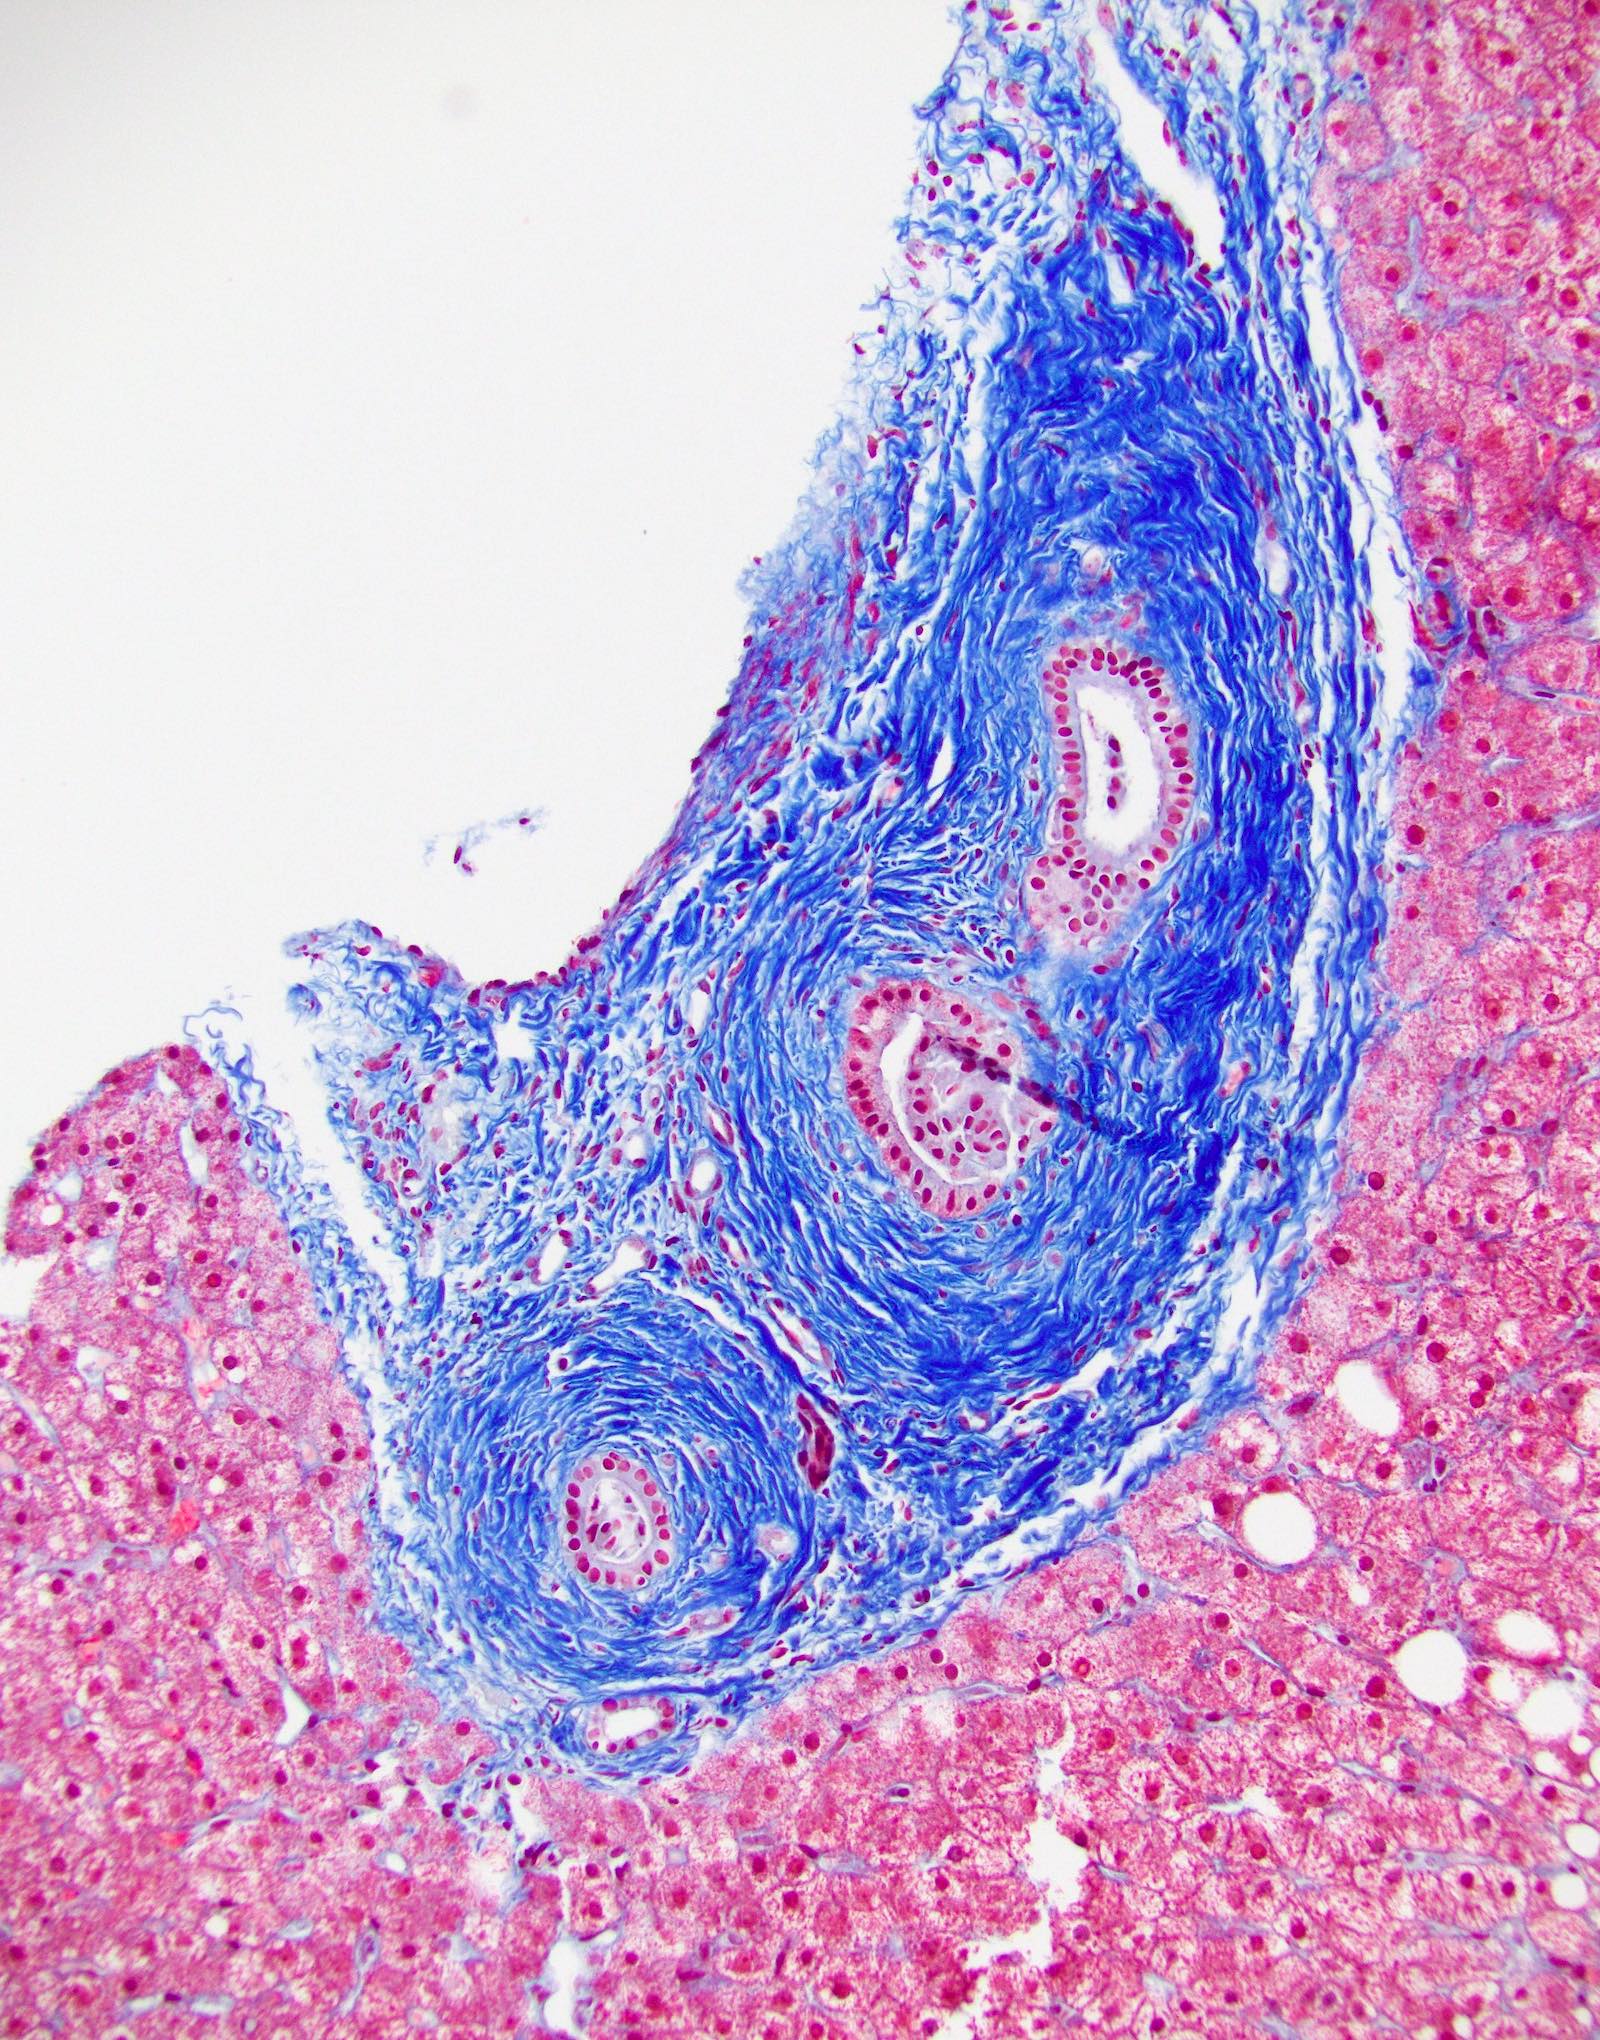

- Vascular changes (Pediatr Transplant 2018; 22:e13124, Am J Transplant 2018;18:1534):

- Obliterative portal venopathy with nodular regenerative hyperplasia-like changes

- Obliterative arteriopathy or isolated arterial "V" lesions (age inappropriate arterial fibrointimal hyperplasia with no T cell mediated rejection) with or without intimal inflammation arterial lesions are associated with subsequent T cell mediated rejection (TCMR), graft failure and C4d positivity; most C4d positive cases show additional histologic features encountered in cAMR such as portal and perivenular inflammation (rejection activity index / RAI 1 - 2) and at least moderate periportal, perivenular or sinusoidal fibrosis (Am J Transplant 2018;18:1534)

Microscopic (histologic) images